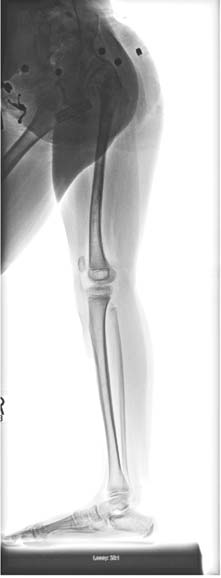

术前前后位和侧位X光片。她既往曾接受超级髋‐超级膝手术,并在4岁时成功接受过一次外固定器延长术。她的腿部长度差异为7厘米。(B) 使用PRECICE 2 8.5毫米 245毫米、转子入路股骨钉进行5厘米延长后的前后位X光片。同时使用半骨骺阻滞板治疗其膝外翻。(C) 此为牵张停止一个月后愈合期的前后位X光片,显示牵开间隙正在由骨组织填充。)